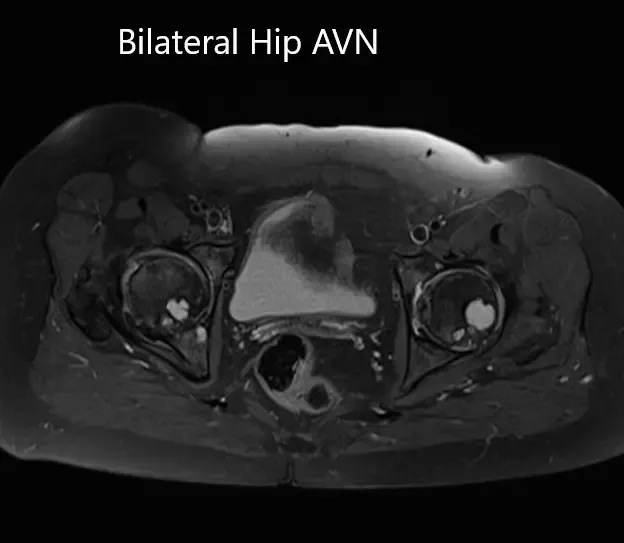

MRI was obtained which showed:

Right Hip Joint: There is a loss of sphericity of right femoral head, involving more than 2/3 of the circumference. In the superior part of the right femoral head, a focal lesion is visualized which is bounded by a serpiginous T1 hypointense margin. The lesion is hypointense on both T1 & T2WI relative to the marrow (Mitchell class – D).

No subchondral fracture is detected. A minimal amount of fluid is seen in the joint cavity. The femoral neck and acetabulum display normal signal intensity. Muscles in view display normal signal intensity.

Left hip joint: Displays similar although less severe changes. The sphericity of the left femoral head is maintained. There is more than 2/3 circumferential involvement of the left femoral head. No subchondral fracture is seen. No joint effusion is seen.

Axial sections of T1WI and T2WI of the pelvis MRI.